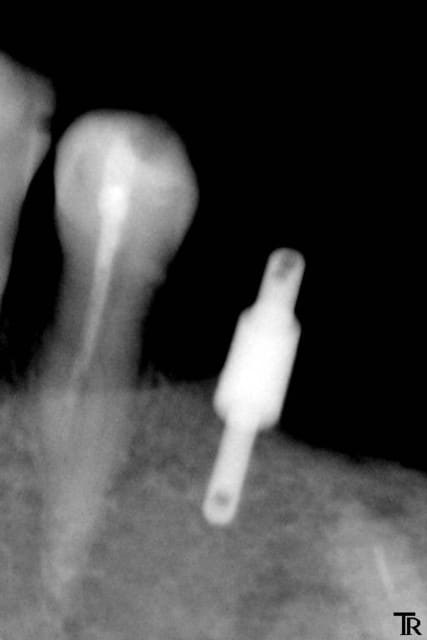

Je suis de nature très prudent, je fore à 12mm. Radio de contrôle, je suis tangent au canal dentaire. Le Kontact doit être mis en sous crestal, même avec le 4.2X10 je ne veux pas faire prendre de risque à ma patiente. Je décide donc de poser un smilea conic à 4.4X10, que je pourrai poser en juxta.

Je réalise toute la séquence opératoire. Je mets des stops à sur tous mes forêts à 10 mm.

3  jauge smilea   10 mm vtcvpx - Eugenol